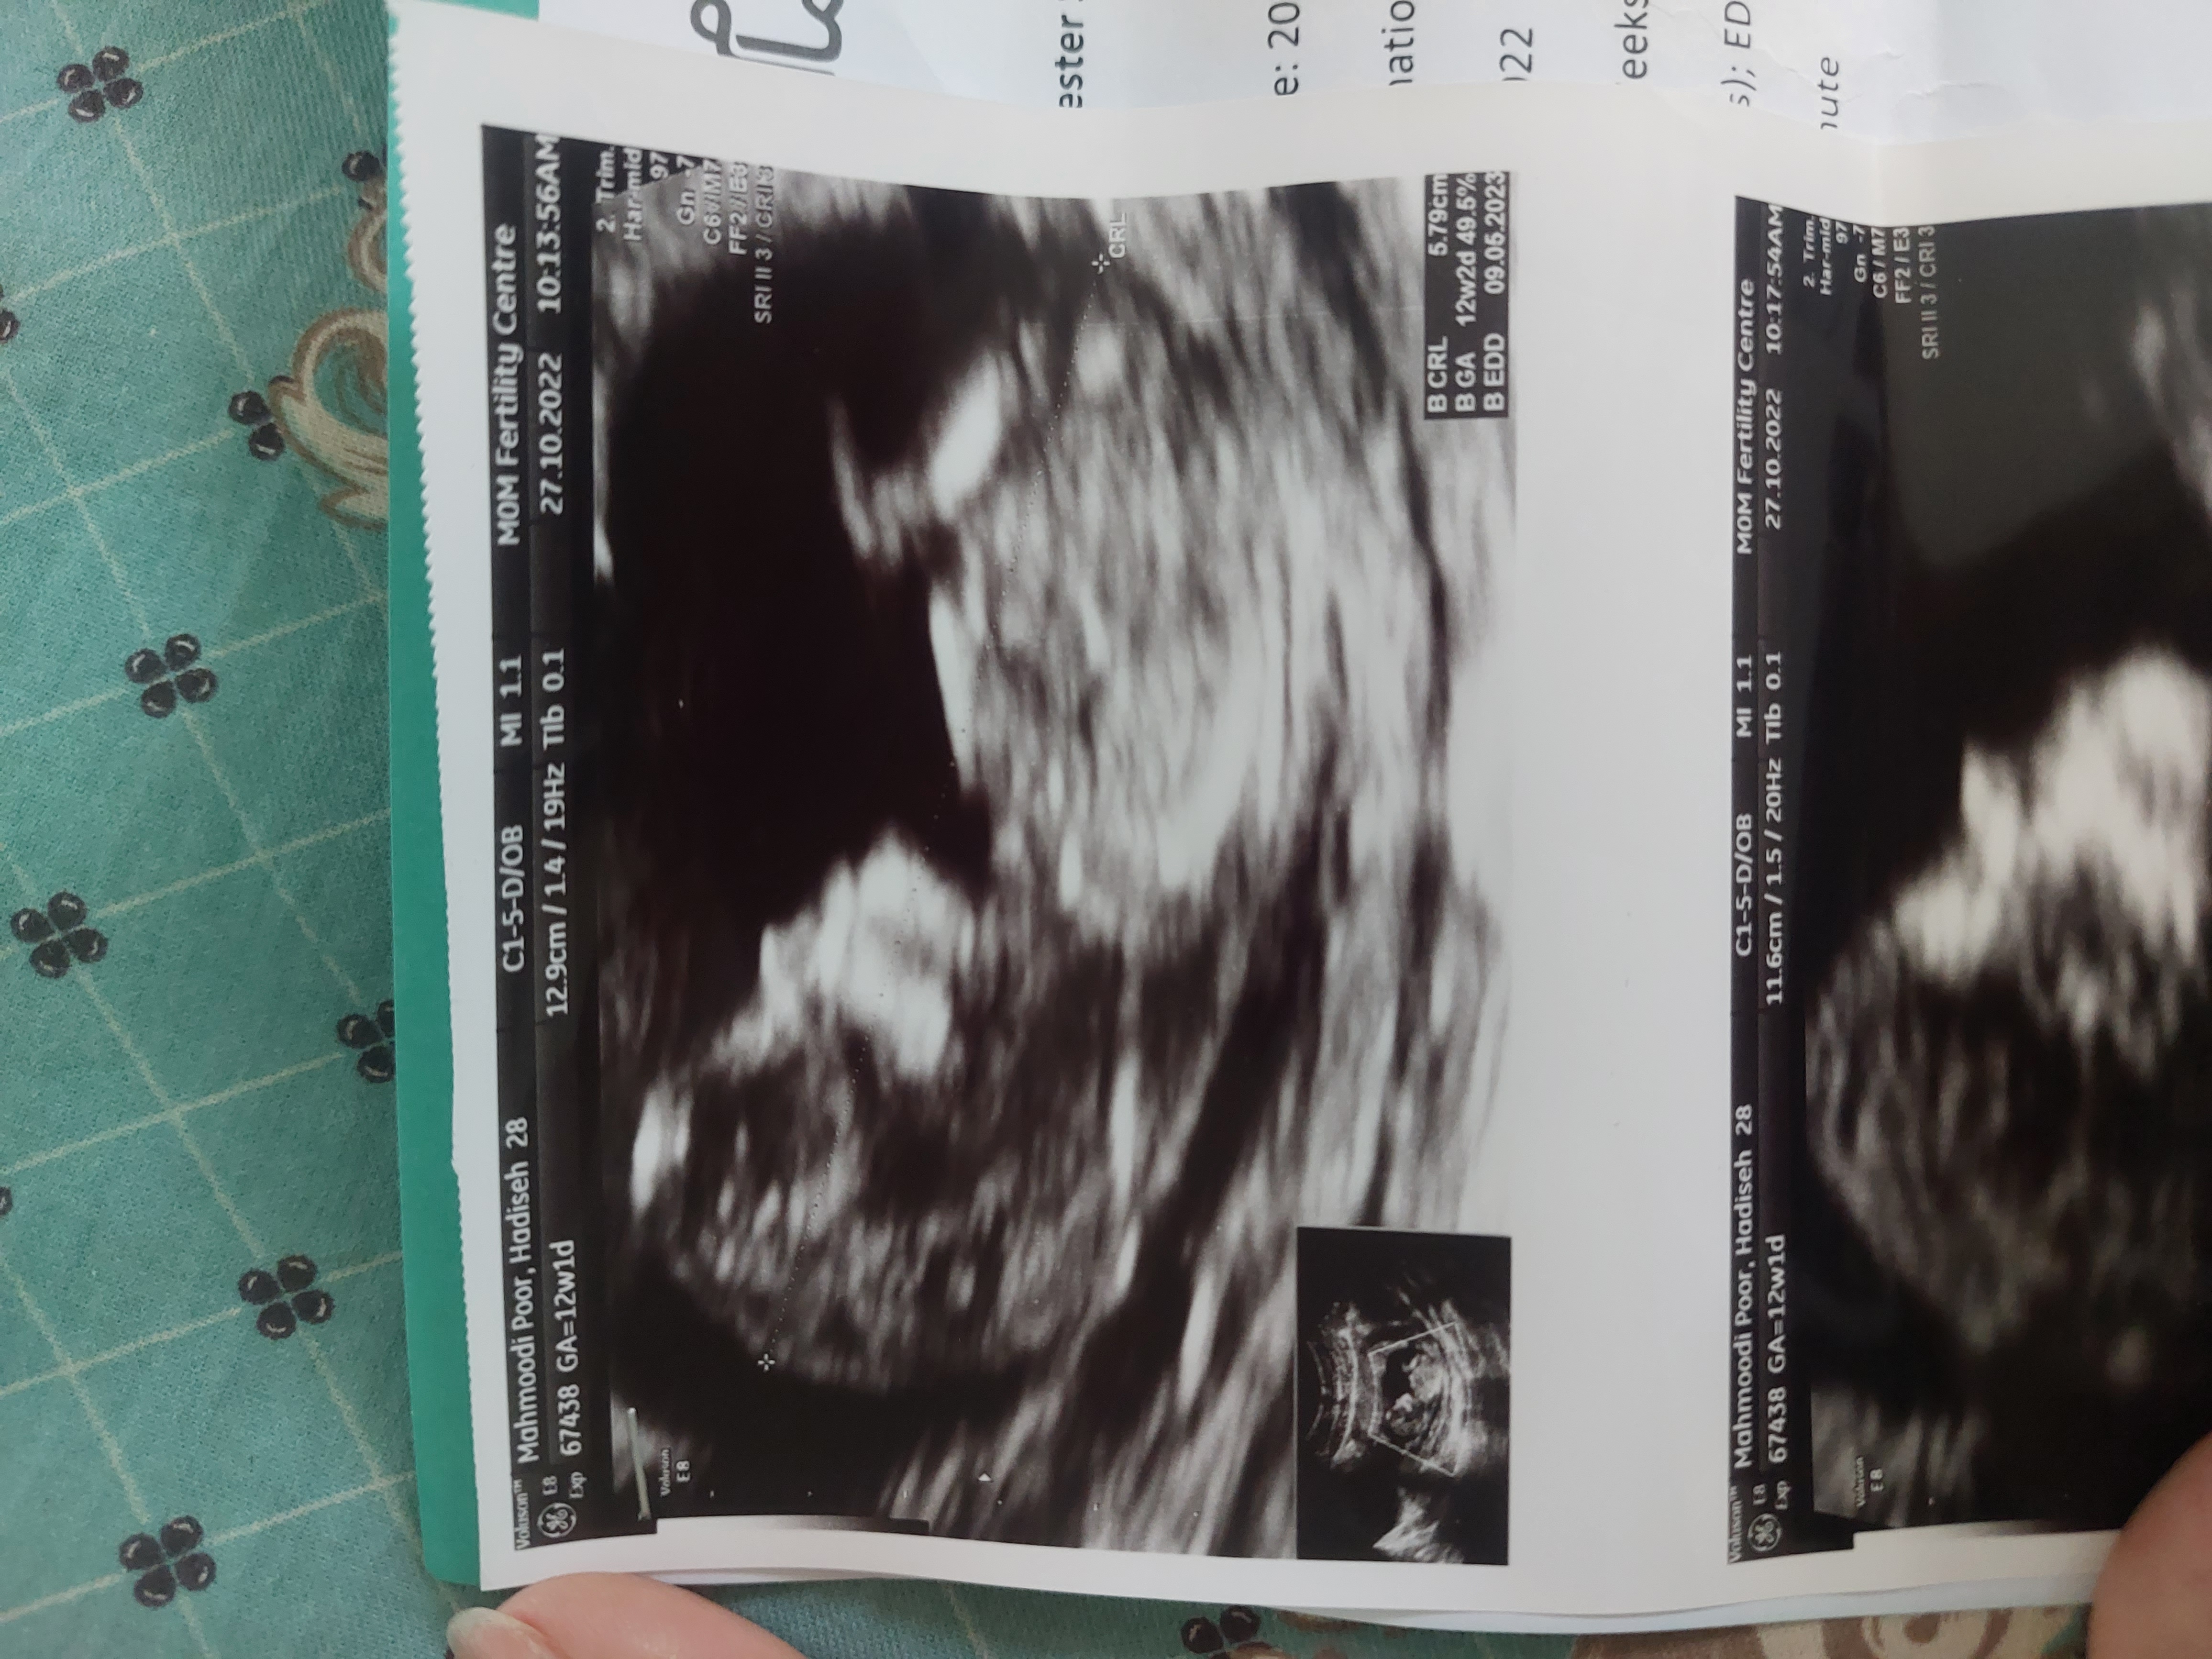

غربالگری اول چقد درصد خطا داره

من  حس میکنم اشتباه گفت  اخه بچه ام خیلی تکون میخورد  بنظرتون گفت از رو لگن دختره  ولی  ۶۰ درصد  گفت قابل تشخیص نیست خیلی تکون میخوره کسی بوده اشتباه شده باشه

برای من رو همون 40 درصد درست گفت... برای منم زیاد تکون می‌خورد... از رو crl ببین چنده کمتر 60 معمولا دختره

برای من رو همون 40 درصد درست گفت... برای منم زیاد تکون می‌خورد... از رو crl ببین چنده کمتر 60 معمولا ...

۱۲ هفته ام من نفهمیدم تو سونو خیلی تکون میخورد یجا نموند